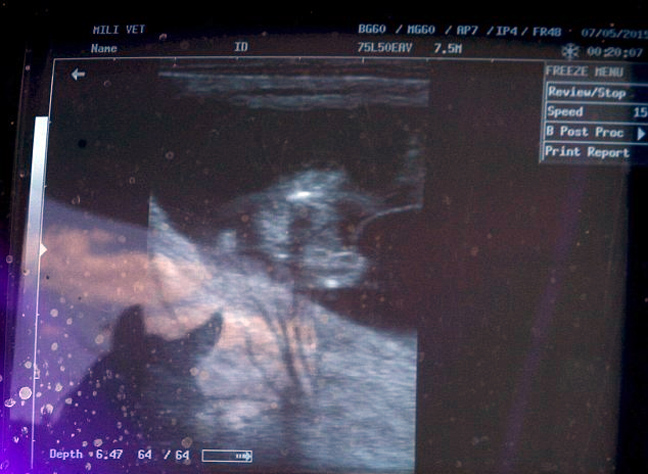

Ο 43χρονος, πρώην παίκτης του πόλο ο ίδιος και κτηνίατρος, εξηγεί πως τα έμβρυα προκύπτουν από την ένωση σπέρματος και ωαρίων των αλόγων με την καλύτερη απόδοση. Το γενετικό υλικό τοποθετείται σε παρένθετες… φοράδες, επιτρέποντας έτσι στα θηλυκά άλογα που έχουν κορυφαίες επιδόσεις στο πόλο να συνεχίσουν να αγωνίζονται χωρίς να εγκυμονούν.

Για 20.000 δολάρια η GeNeTec συλλέγει τα ωάρια αλόγων με pedigree, τα γονιμοποιεί και τοποθετεί τα έμβρυα στις παρένθετες μητέρες.

«Το σημαντικό στοιχείο στην εμβρυομεταφορά είναι πως η δωρήτρια φοράδα συνεχίζει τις αθλητικές τις δραστηριότητες, κάτι που σημαίνει πως δεν χρειάζεται ποτέ να σταματήσει να παίζει πόλο», συμπληρώνει ο Sporleder.